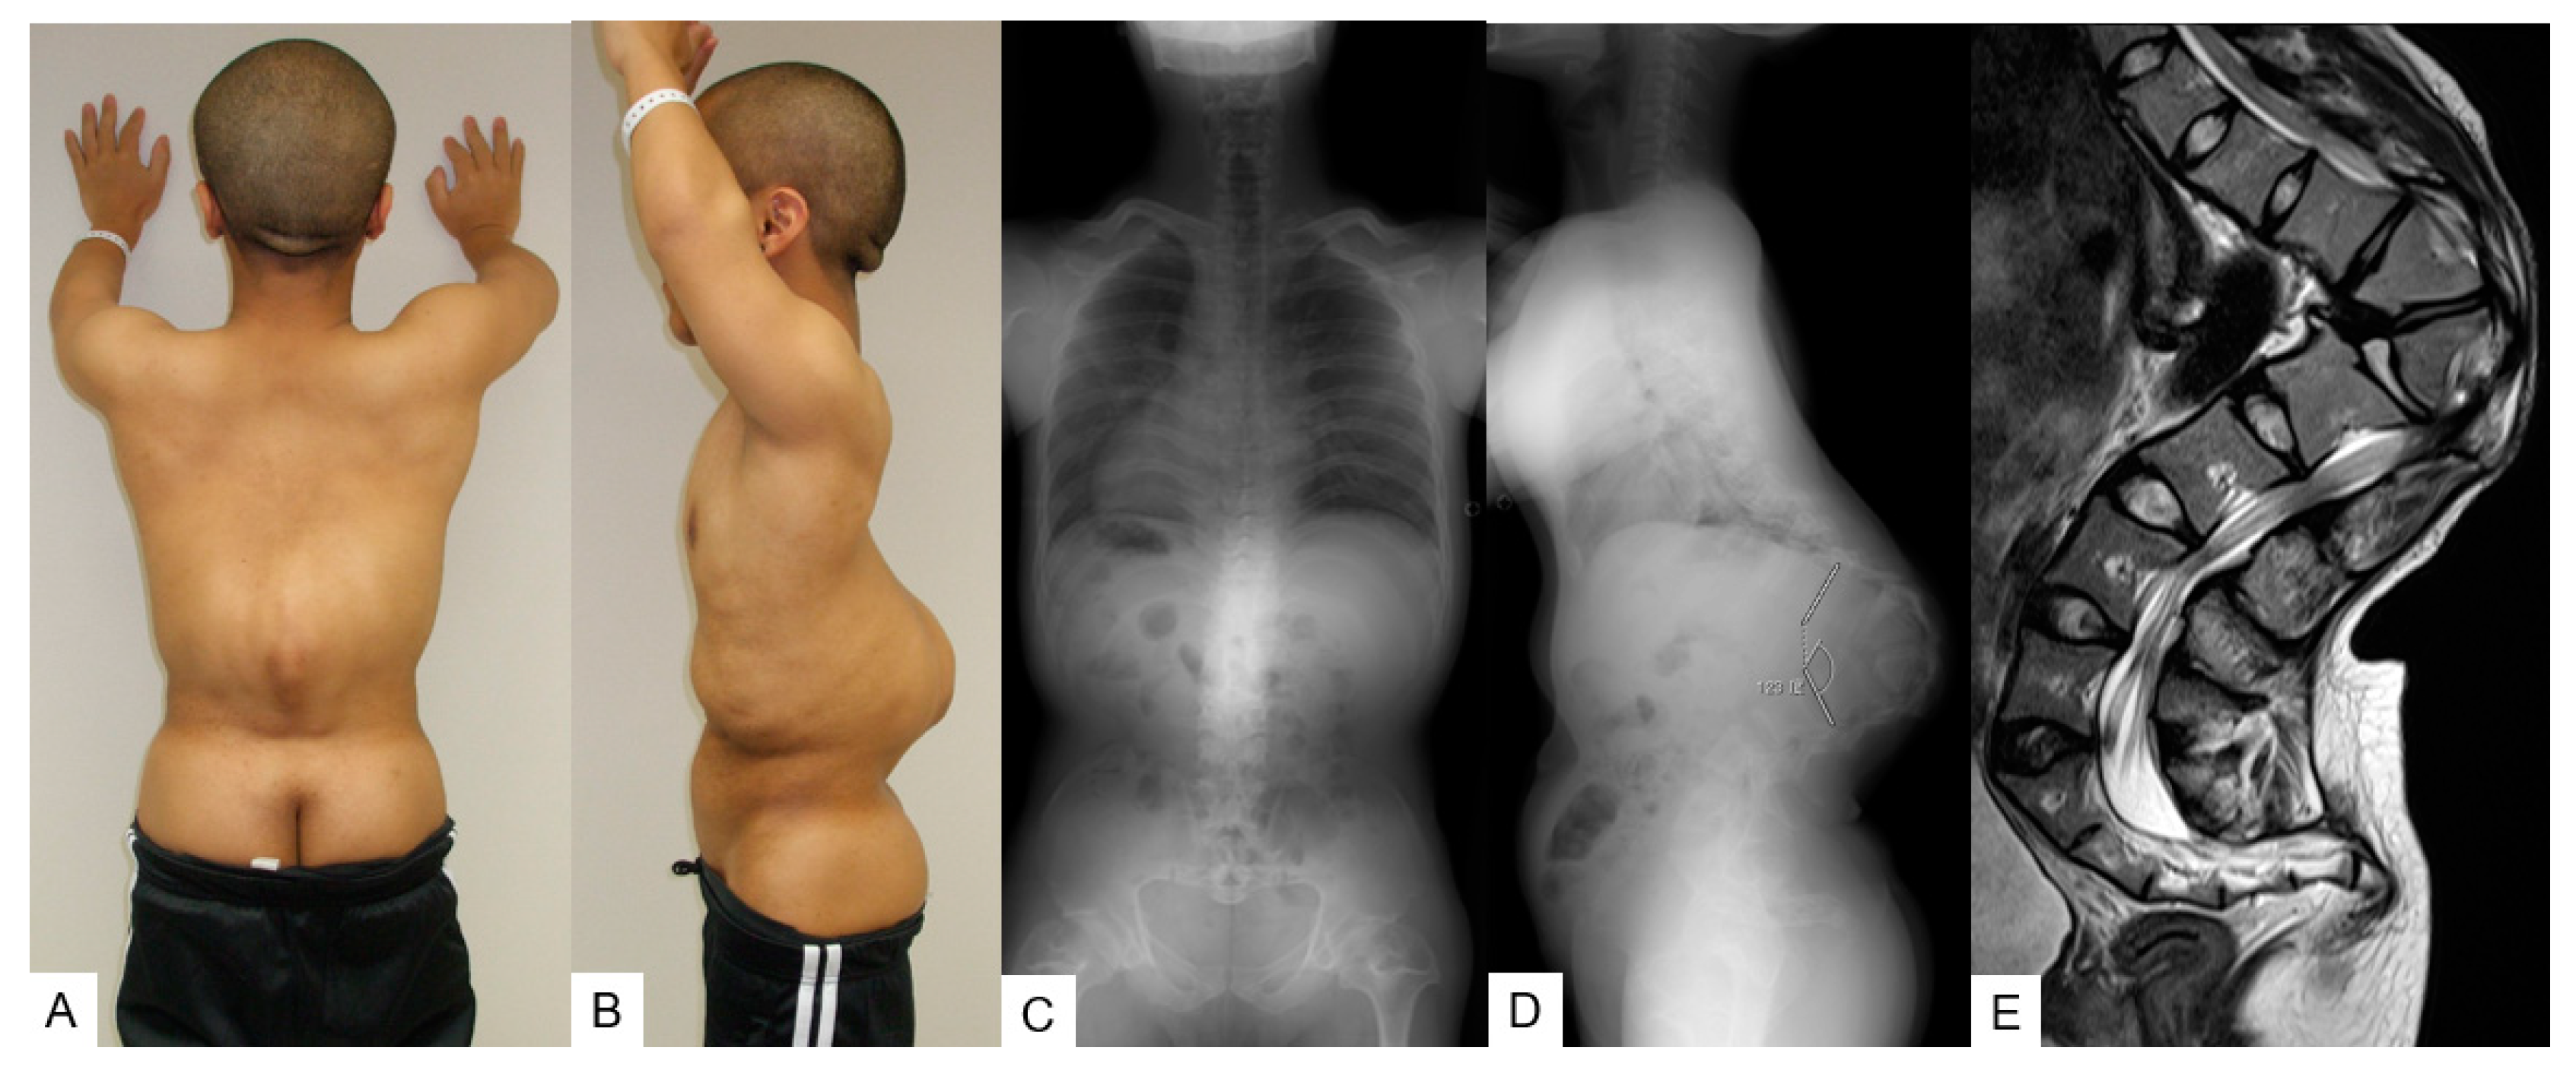

3.2.1. Patient History

3.2.2. Physical Examination

3.2.3. Preoperative Imaging